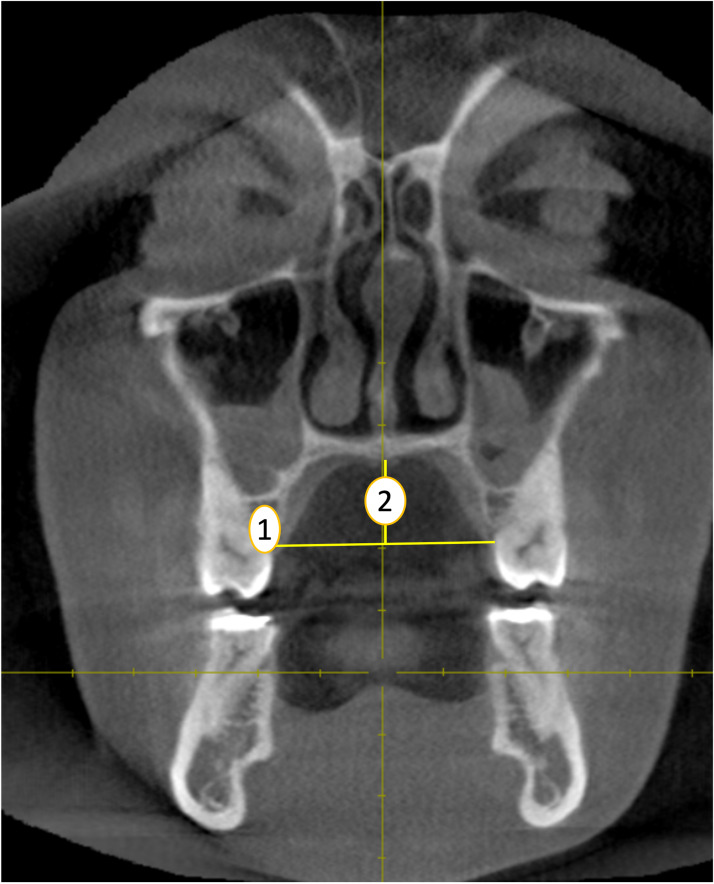

Palatal width (PW): The distance between the cemento-enamel junction of the left and right first molars from coronal plane (ref. Spradley & Jantz, 2011) (Fig. 3, point 1).

Palatal height (PH): The distance of the perpendicular line drawn from midpalatal region intersecting the horizontal line connecting the cemento-enamel junction of the left and right first molars from coronal plane. (ref. Spradley & Jantz, 2011) (Fig. 3, point 2).